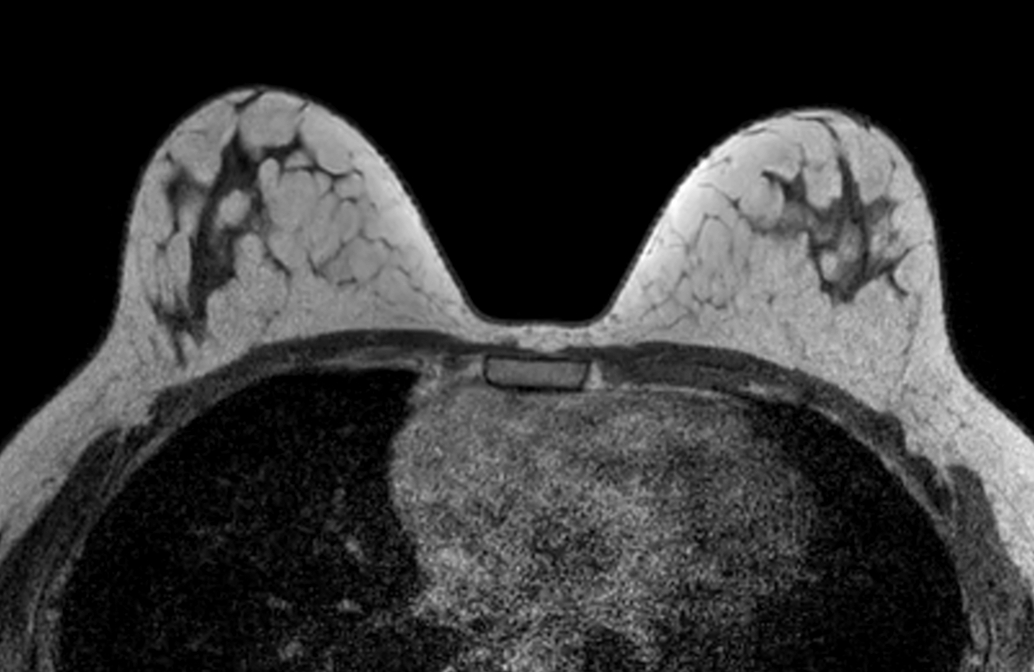

Axial mDIXON XD FFE (In Phase) - Dyn 1